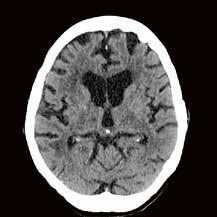

Gehirnblutung oder Gefäßverschluss

Handelt es sich um eine intrakranielle Blutung oder ist ein großes Gefäß verschlossen?

Ein Schlaganfall kann auf unterschiedliche Ursachen zurückzuführen sein. Deshalb ist es besonders wichtig, in kürzester Zeit über eine aussagekräftige Diagnostik zu verfügen.

Mit der Deep-Learning-basierten Auto-Stroke-Solution bringt Canon eine Lösung auf den Markt, die nicht nur selbstständig Bilder erstellt, sondern auch noch den Befundbericht dazu liefert.

Mit der Auto-Stroke-Solution präsentiert Canon eine Lösung, die in der Lage ist, ohne einen einzigen Klick unterschiedliche Arten von Schlaganfällen zu bestimmen und automatisiert eine detaillierte Auswertung zu erstellen. Um den Zustand des Schlaganfalls vollständig zu charakterisieren, analysiert das System, das auf Canons ebenfalls neuer Automation-Platform läuft, selbstständig CT-Scans. Den Notfallund Stroke-Teams werden in kürzester

Zeit Informationen zur Verfügung gestellt, die bei der klinischen Bewertung und Behandlung von Schlaganfällen helfen. „Die Auto-Stroke-Lösung integriert drei Schlaganfall-Applikationen, um sicherzustellen, dass die Untersuchung eine exakte Abbildung dessen liefert, was im Patienten vor sich geht“, beschreibt Michael Glasa, Produktmanager Healthcare IT und Manager Sales Support CT bei Canon Medical Systems, das neue System.

Diagnostik ohne Klick

Wenn die Zeit drängt, helfen die AutoStroke-Deep-Learning-Algorithmen bei Hirninfarktpatienten schnell, unterschiedliche Variationen einer intrakraniellen Blutung oder große Gefäßverschlüsse zu lokalisieren beziehungsweise die Penumbra und den potenziellen Infarktkern anzuzeigen. Denn die Kliniker benötigen schnellstmöglich Informationen, um in kurzer

Zeit fundierte Behandlungsentscheidungen treffen zu können. „Mit AutoStroke fassen wir nicht nur das Untersuchungsergebnis in einem Bericht zusammen, sondern stellen auch noch sicher, dass die Informationen ebenfalls auf mobilen Geräten, PCs oder im PACS eingesehen werden können“, erklärt Michael Glasa die Funktionsweise der Lösung für Schlaganfall-Netzwerke. Welche Therapie bei einem Schlaganfall die beste Option darstellt, hängt von vielen Faktoren ab. Speziell bei Verschlüssen großer Gefäße (LVO –Large Vessel Obstruction) scheint eine endovaskuläre Intervention im Vergleich zur systemischen Lyse bessere Ergebnisse zu liefern. Da im Falle einer Verlegung der Patient*innen eventuell Transportzeiten berücksichtigt werden müssen, ist eine möglichst exakte Diagnostik noch vor Ort von besonderem

Vorteil. Für die systemische Lyse gilt ein Zeitfenster von drei bis viereinhalb Stunden und für die endovaskuläre Intervention bis zu sechs Stunden – in Ausnahmesituationen bis zu 16 Stunden. Je früher nach dem Symptombeginn eine Reperfusion erreicht wird, desto erfolgversprechender sind bei beiden Therapiearten die Aussichten auf eine Besserung der Symptomatik.

Michael Glasa: „Eine schnelle Triage ist für den Patienten ausschlaggebend. Mit Auto-Stroke beschleunigen wir den gesamten Befundprozess. In weniger als 60 Sekunden analysieren die Algorithmen parallel die Bilder von bis zu drei unterschiedlichen Untersuchungen und die Befundberichte werden vollkommen automatisiert angefertigt, ohne dass eine Maus oder eine Tastatur bedient werden müssen.“

jedes einzelne Pixel. Die Software stellt sogar selbstständig fest, ob die Untersuchung mit oder ohne Kontrastmittel durchgeführt wurde.“ Handelt es sich um eine Untersuchung ohne Kontrastmittel, sucht Auto-Stroke nach einer Gehirnblutung und erkennt selbstständig die unterschiedlichen Arten: subdural, epidural oder subarachnoidal. Wurde bei der Untersuchung Kontrastmittel verwendet, sucht die Maschine nach einem Gefäßverschluss. Und auch Perfusionsstudien werden automatisiert ausgewertet. Sowohl die ausgewerteten Bilder als auch die maschinell erstellten Reports werden direkt ins PACS geschickt. Man kann das System auch so einstellen, dass es den Report per E-Mail entweder an die behandelnden Ärzt*innen oder zusätzlich an die Radiolog*innen versendet. Im PDF-

Befundbericht sind in den Bildern die verdächtigen Areale markiert beziehungsweise farblich hervorgehoben, so dass leicht zu erkennen ist, wo eine Veränderung stattgefunden hat.

Hohe Sensitivität und Spezifität

Trotz der enormen Verlässlichkeit des Algorithmus liegt es an den weiterbehandelnden Ärzt*innen, das automatisiert erstellte Ergebnis zu validieren. Für die Analyse intrakranieller Blutungen wurde der Deep-LearningAlgorithmus anhand von mehr als 10.000 Fällen trainiert. Die gemessene Sensitivität beträgt 92 Prozent und die Spezifität erreicht einen Wert von 97,5 Prozent. Bei der Unterscheidung von Gefäßverschlüssen liegen die Werte von Sensitivität und Spezifität

bei jeweils 98 Prozent. Bei der CT-Perfusionsmessung nutzt die Anwendung die Bayesischen CTP+-Algorithmen, um die Penumbra und den Infarktkern ohne einen einzigen Klick zu quantifizieren. Dabei können nicht nur 2D-, sondern auch 4D-Studien gleichermaßen ausgewertet werden. Der große Vorteil von Auto-Stroke besteht darin, dass die Kliniker*innen innerhalb kürzester Zeit einen kompletten Befundbericht zugeschickt bekommen, um schnell die richtige Therapie-Entscheidung treffen zu können. Das System ist in der Lage, innerhalb eines Zeitraums von etwa 30 bis maximal 60 Sekunden automatisiert und mit hoher Zuverlässigkeit Schädel-CT-Scans auszuwerten und unterschiedliche Arten von Schlaganfällen zu differenzieren. //